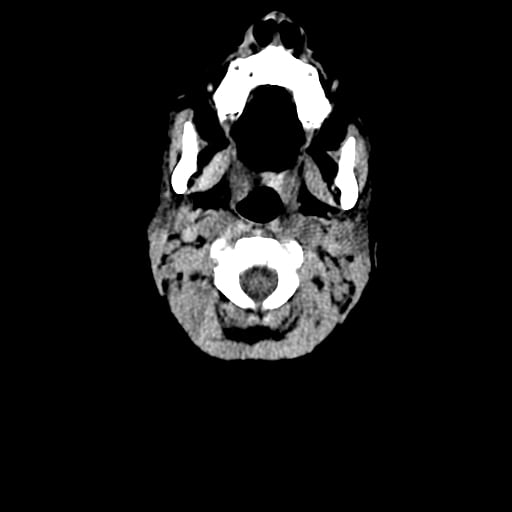

Age: 1

Sex: Male

Indication: Fall